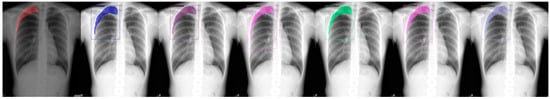

Figure 5.

From left to right: Ground Truth, ResNet50 (COCO), ResNet101 (COCO), ResNeXt101 (COCO), ResNet50 (LVIS), ResNet101 (LVIS), and ResNeXt101 (LVIS). This patient had a large area of pneumothorax in their left chest.

We chose a few examples to demonstrate the capabilities of various models. These images consisted of X-ray images of pneumothorax patients with different areas of disease inflicted. The inclusion of multiple positions and areas in the figures lets us observe the possible outcomes and the differences between the models. In Figure 3 and Figure 6, the patients had pneumothorax on the right side of their chest, with the patient in Figure 6 only affecting the top part, while the patient in Figure 3 had pneumothorax on the outside wall of their right lung. In Figure 4, Figure 5 and Figure 7, the patients had pneumothorax in the left side of their chest, while the patients in Figure 4 and Figure 5 had the upper part of their left lung mostly collapsed, indicating a serious issue of pneumothorax disease. In Figure 5, there are cavity areas at the bottom part, too. In the same image, the ground truth included a portion protruding below the area of the top detection portion due to the late-stage pneumothorax with most of the upper part of the lung collapsing, and all models were unable to detect the cavity of the protruded part. In Figure 7, the patient is seen with a fixation, with the pneumothorax affecting the top left lung, albeit with a smaller area.